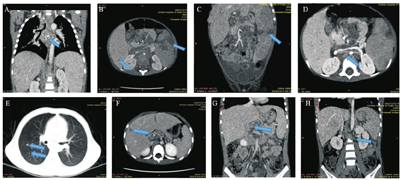

入院查体:患儿神清,精神差,无特殊面容,双侧颈部触及蚕豆大小淋巴结,心肺查体无阳性体征,腹部膨隆,腹壁静脉显露,肝肋下5 cm,剑突下4 cm,质中,无触痛,脾肋下5 cm,质中,肠鸣音正常。实验室检查结果见表1。尿培养2次均阴性;入院第5天普通血培养无细菌生长;X线胸片示两肺片状渗出影,心影大,两侧胸腔积液;胸腹部CT(图1)及B超示肝脾肿大,肝门区至胰腺周围多发实质占位性病变,脾内多发实质占位性病变,腹腔内多发实质欠均质占位性病变,胸腔积液、心包积液、腹腔积液。入院后予头孢哌酮舒巴坦抗感染、氟康唑抗真菌,输注血浆、纤维蛋白原、悬浮红细胞,白蛋白等对症支持治疗,外送血病原体二代测序第4天回报马尔尼菲蓝状菌感染,患儿精神仍差伴高热,凝血示肝功能衰竭,第3天改用伏立康唑静脉滴注抗真菌。第6天患儿热峰下降,第9天患儿体温正常,复查血常规示血红蛋白107 g/L,血小板81×109/L,凝血功能:凝血酶原时间13.8 s,国际标准化比值1.07,患儿病情平稳,第10天行腹腔淋巴结、肠系膜淋巴结病理活检均见孢子(图2)。第15天血真菌培养示马尔尼菲蓝状菌生长。静脉滴注伏立康唑25 d复查血真菌(1,3)-β-D葡聚糖138.5 pg/mL;B超示肝大较前缩小,腹腔内占位性病变减小,少量腹腔积液、未见胸腔积液,改为伏立康唑口服治疗。患儿治疗5个月后复查肝功能、凝血功能未见异常;血培养、尿培养、3次胃液找抗酸杆菌均阴性;全身骨扫描未见异常,胸部CT示渗出较前吸收,腹部增强CT示肝脾多发低强化灶较前减少,血病原体二代测序未检出真菌。患儿伏立康唑治疗6个月后停用,随访至今无复发。

A-D:例1患儿上腹部增强CT;A:箭头示纵隔淋巴结肿大伴钙化,B、C:箭头示肝脾内低强化灶,D:箭头示后腹膜淋巴结。E-H:例2患儿胸部增强CT;E:箭头示肺部小结节,F:箭头示肝内低密度灶,G:箭头示肝门区淋巴结,H:箭头示后腹膜淋巴结。

入院查体:患儿全身皮肤巩膜轻度黄染,未见皮疹及出血点。双侧颈部触及蚕豆大小淋巴结。心肺查体无阳性体征,腹软,肝肋下约3 cm,质软(+),脾肋下未触及。实验室检查结果见表1。铜蓝蛋白正常范围;自身抗体提示抗核抗体弱阳性,余阴性;尿培养2次均阴性;入院第5天普通血培养无细菌生长;第2天普通痰培养无细菌生长,无嗜血杆菌生长。血(1,3)-β-D葡聚糖91.8 pg/mL;胸腹部CT示(图1)双肺多发小结节,右肺中叶胸膜至胰腺周围多发实质占位性病变,脾内多见纤维条索灶,肝、脾、双肾多发低强化影,肝门区及后腹膜见多发增大淋巴结。少量腹腔积液,盆腔少量积液。入院后予美罗培南抗感染,第4天血病原体二代测序提示马尔尼菲蓝状菌感染,加伏立康唑静脉滴注抗真菌,第8天患儿体温正常,骨髓培养示马尔尼菲蓝状菌生长,第9天再次发热,咳嗽增多,病原体示腺病毒、肺炎支原体感染,加用阿奇霉素抗肺炎支原体感染,甲泼尼龙抗炎,丙种球蛋白免疫支持等治疗,第15天患儿未再发热,咳嗽减少。患儿静脉滴注伏立康唑14 d后改为伏立康唑口服治疗,治疗1个月后患儿皮肤无黄染,无咳嗽,肝肿大较前缩小。随访6个月复查血常规、CRP正常范围,肝功能除谷氨酰转移酶(99 U/L)轻度升高外,其他指标均在正常,胸部CT提示双肺结节大部分吸收,伏立康唑治疗6个月后停用。现复查肝功能指标均正常,无复发,仍随访中。